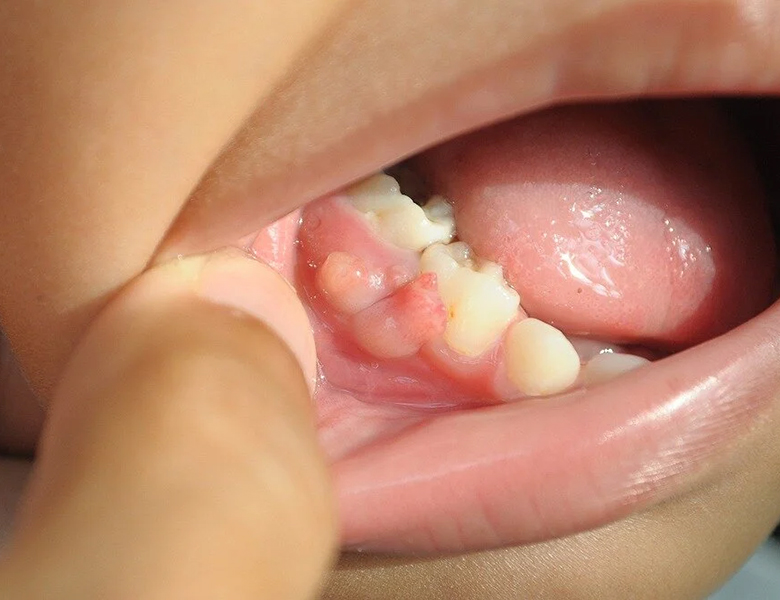

歯茎のポチッとした膨らみ(フィステル/根尖性歯周炎)

歯茎に白いニキビのようなデキモノができ、潰れると膿が出て、また膨らむ……という症状です。

過去に神経を抜いた歯の内部で細菌が繁殖したり、神経が自然に死んでしまったことで、膿が骨を突き破って出口(フィステル)を作っています。

痛みがないことも多いですが、実は「歯の根の先」に膿が溜まっているサインです。

当院の対応

マイクロスコープで根管内を精密に清掃する「精密根管治療」が必要です。

放置すると周囲の骨を溶かしてしまうため、早めの受診が大切です。